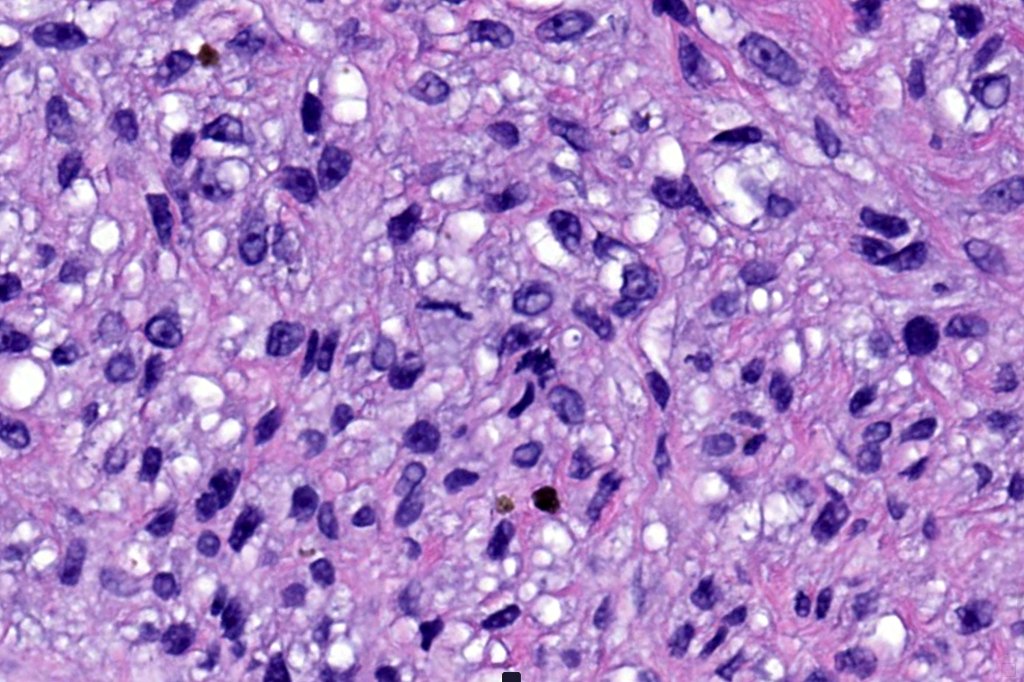

Histological features

•Develops within a precursor lesion as one or more nodules of epithelioid or spindled cell melanoma

•Nuclear pleomorphism with prominent nucleoli, mitotic activity & abnormal mitoses

•Necrosis sometimes present

•Occasionally perineural infiltration or vascular invasion seen